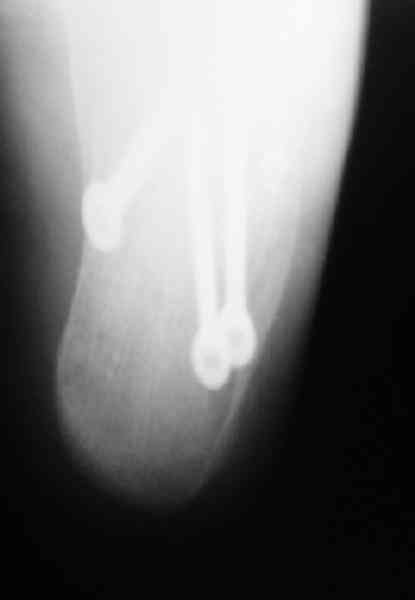

Открытый и закрытый способы лечения.

Если нет опыта в остеосинтезе пяточной пластиной то лучше начать с экскохлеации полости кистозного образования и заполнения его остеоиндукторами Коллапан, Тутопласт, etc.Закрытая репозиция с рентгенконтролем на столе и перкутанная фиксация спицами пяточного бугра с фиксацией в эквинусе могут дать вполне приемлемый результат.

Вправление задней фасеты с восстановлением таранно-пяточного угла возможно минимально-инвазивным методом Essex-Lopresti - под ЭОП или графическим контролем введенной в пяточный бугор толстой спицей или стрежнем Штеймана, которые служат рычагом. Для удержания вводим несколько тонких спиц Киршнера, фиксация в эквинусе.Подробнее в Margo anterior 1-2 2000\издание АО Матис в России, на сайте www.mathys.ru в архиве есть все выпуски. Метод внедрен у нас с 2000 года и дает неплохие результаты.

Действительно архив Margo Anterior начинается с 2001 года.Но я могу эту статью по лечению переломов пяточной кости,очень обстоятельную, санировать и выслать мылом на ваш адрес или разместить на rapidshare ru и указать ссылку на форуме. несколько тонких спиц вводятся в разных направляениях при многофрагментарных переломах иногда через подтаранный сустав для удержания репозиции. Их и стержень удалем через 6 недель.